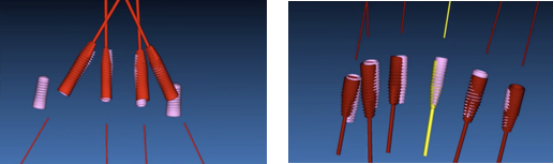

· 手术过程采用士卓曼360数字化序列导板

· 制作放射导板,进行数字化导板设计。

· 上下各计划植入6颗种植体。其中14、24种植体倾斜植入,15、25经牙槽嵴顶上颌窦提升植骨,其余牙位无需植骨。

种植体位置设计,可见上前牙唇侧骨量过丰满,需适量去骨。同时上下颌均需要截骨处理。

· 上下颌士卓曼360数字化导板 +预成临时修复体设计图。

· 士卓曼360导板包括:骨支持的基部导板 、牙支持的辅助导板 、就位于基部导板的种植导板 以及就位于基部导板的预成临时修复体组成。

· 上下颌计划行即刻种植,各植入六颗straumann钛锆种植体并行即刻修复。

· 下颌士卓曼360数字化序列导板+预成临时修复体

· 全程植入导板就位于基部导板上,固位钉固定,引导种植体植入。

· 上颌360数字化序列导板+预成临时修复体

· 全程导板就位,引导种植体植入,安装复合基台。

· 植入精度分析,误差较小。